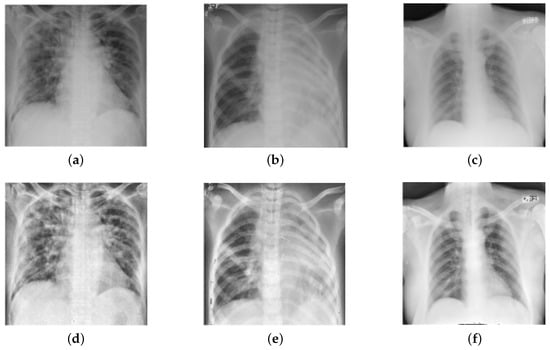

Image Enhancement: Image enhancement is frequently used in the biomedical image processing domain to improve image quality [38,39]. Therefore, in this study, we performed the image enhancement by employing bilinear interpolation (BI) followed by the contrast-limited adaptive histogram equalization (CLAHE) technique. Initially, BI was applied to replace the missing pixel by computing a weighted average of the nearest boundary pixels [40]. Then, CLAHE was employed for contrast enhancement that prevents over-enhancement of noise present in the images [41,42], thereby, facilitating better diagnosis. Figure 3 depicts the outcomes of the preprocessing stage (BI and CLAHE).

Figure 3.

Results of image enhancement (BI and CLAHE): (a–c) indicate original images, (d–f) indicate enhanced images.